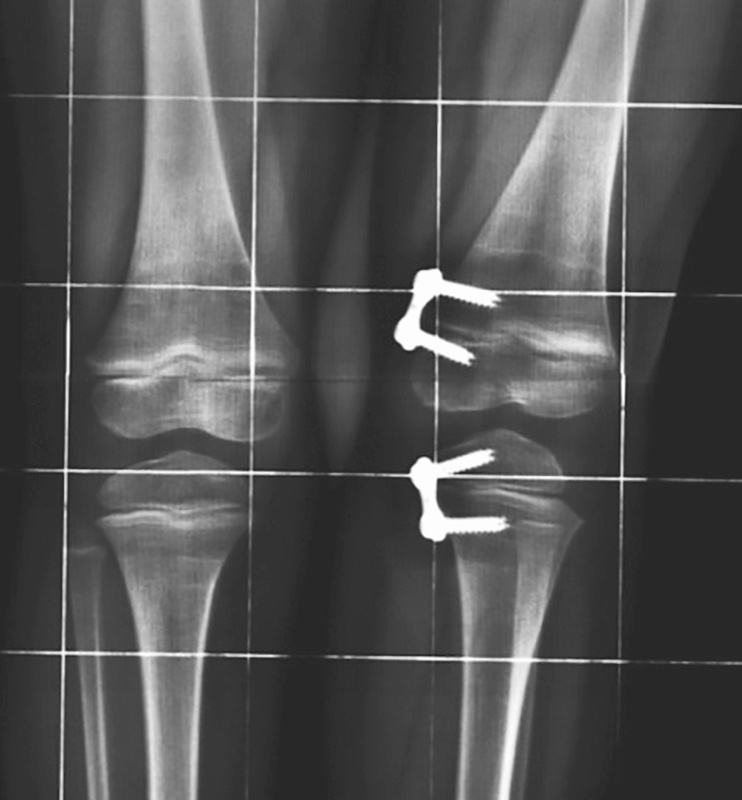

Il trattamento chirurgico viene generalmente praticato mediante emiepifisiodesi o mediante osteotomia correttiva. L’emiepifisiodesi è una procedura chirurgica che consiste nell’arrestare la cartilagine di accrescimento sul lato convesso della deformità, mantenendo l’accrescimento sul lato concavo, fino al riallineamento del segmento scheletrico affetto. Nel ginocchio varo viene transitoriamente bloccato l’accrescimento della cartilagine esterna distale del femore e prossimale della tibia per favorire il riallineamento mediante l’attività della porzione mediale della cartilagine. Tale opzione chirurgica è da preferire all’osteotomia nei pazienti scheletricamente immaturi in cui, ragionevolmente, è presente un periodo residuo di accrescimento di almeno 2 anni 3. Si preferisce tuttavia eseguire l’intervento in prossimità del termine dell’accrescimento per evitare ipercorrezioni iatrogene. L’emiepifisiodesi, che in passato veniva realizzata mediante l’utilizzo di cambre metalliche applicate a ponte della cartilagine di accrescimento, viene attualmente praticata mediante la tecnica descritta da Stevens 4 che ha proposto l’utilizzo di una piccola placca extraperiostale fissata con 2 viti, comunemente conosciuta come placca a 8 (8-plate), da applicare a ponte della cartilagine di accrescimento. Il vantaggio di questa metodica consiste nella facile applicazione mediante un’incisione limitata e un’agevole rimozione dopo aver ottenuto la correzione della deformità. Le possibili complicazioni, peraltro poco frequenti, sono rappresentate dall’insufficiente correzione, dall’ipercorrezione, dalla rottura delle viti, dalla prematura chiusura della cartilagine di accrescimento e dalla recidiva della deformità dopo la rimozione della placca.

La procedura chirurgica correttiva, da effettuare nei casi persistenti, nelle forme adolescenziali e nei casi secondari ad altre patologie (come ad esempio affezioni genetiche, displasie ossee o patologie dismetaboliche (Fig. 7), prevede una emiepifisiodesi delle cartilagini di accrescimento coinvolte mediante placche a 8, allo scopo di bloccare l’accrescimento della cartilagine interna distale dell’osso e/0 prossimale della tibia e favorire il riallineamento del segmento scheletrico10 (Fig. 8).